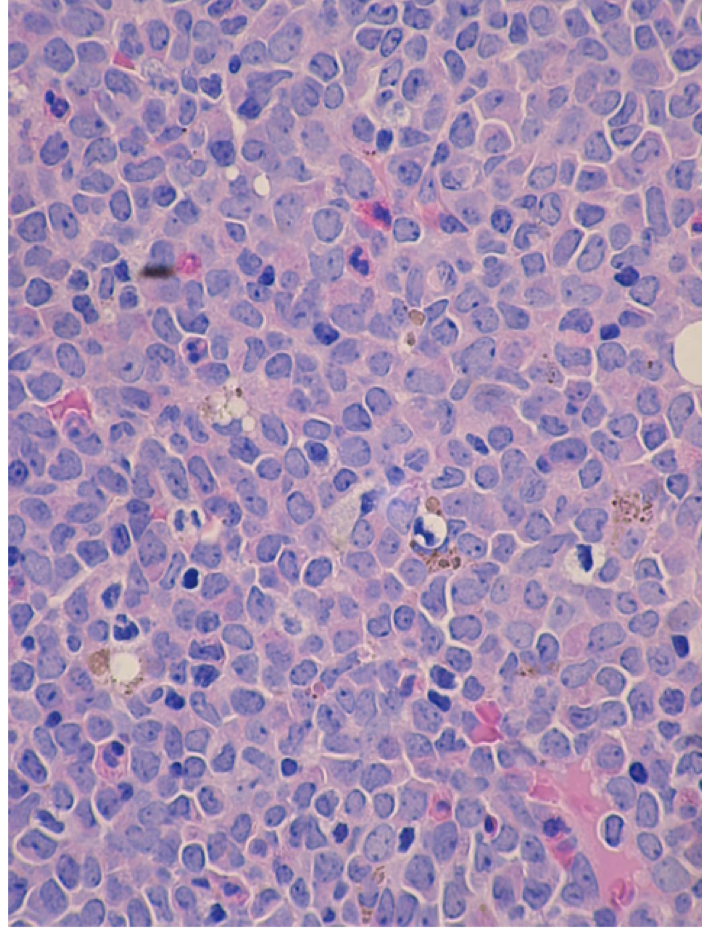

11

Q

source?

what do you see?

diagnosis?

A

• bone marrow biopsy

• monotonous population of mononuclear cells

• AML